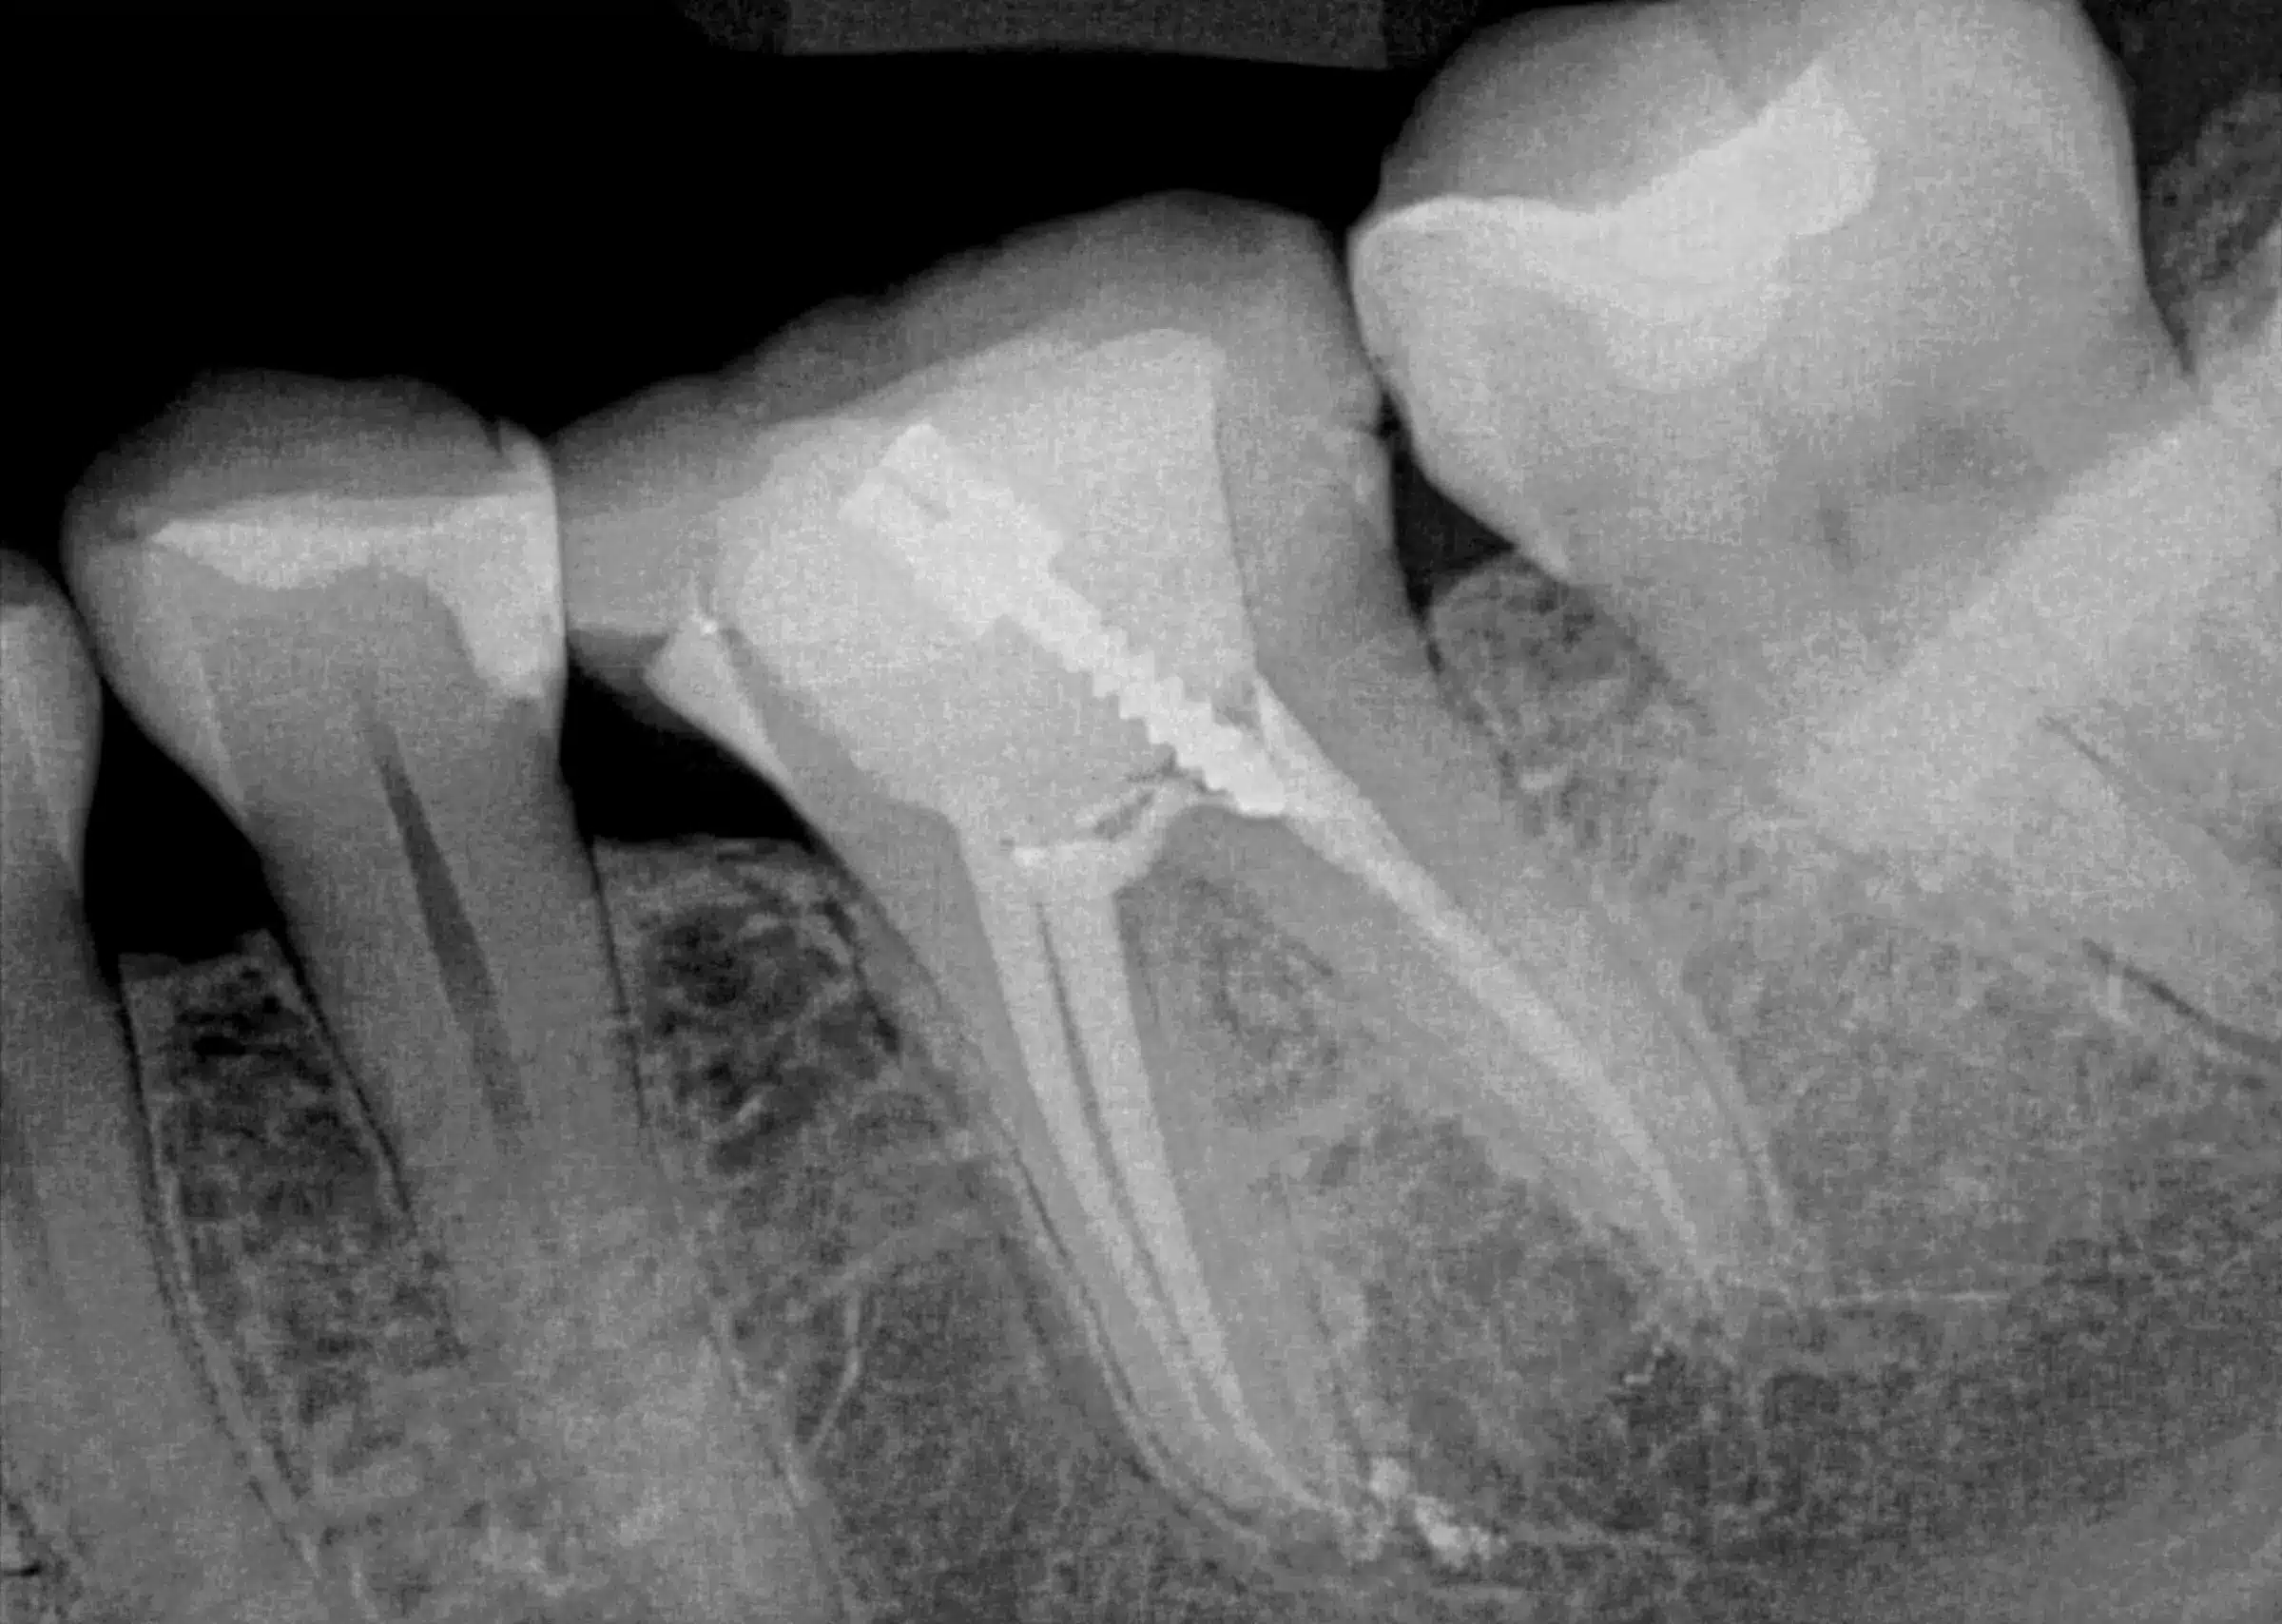

A root canal treatment is designed to eliminate bacteria from the infected root canal.